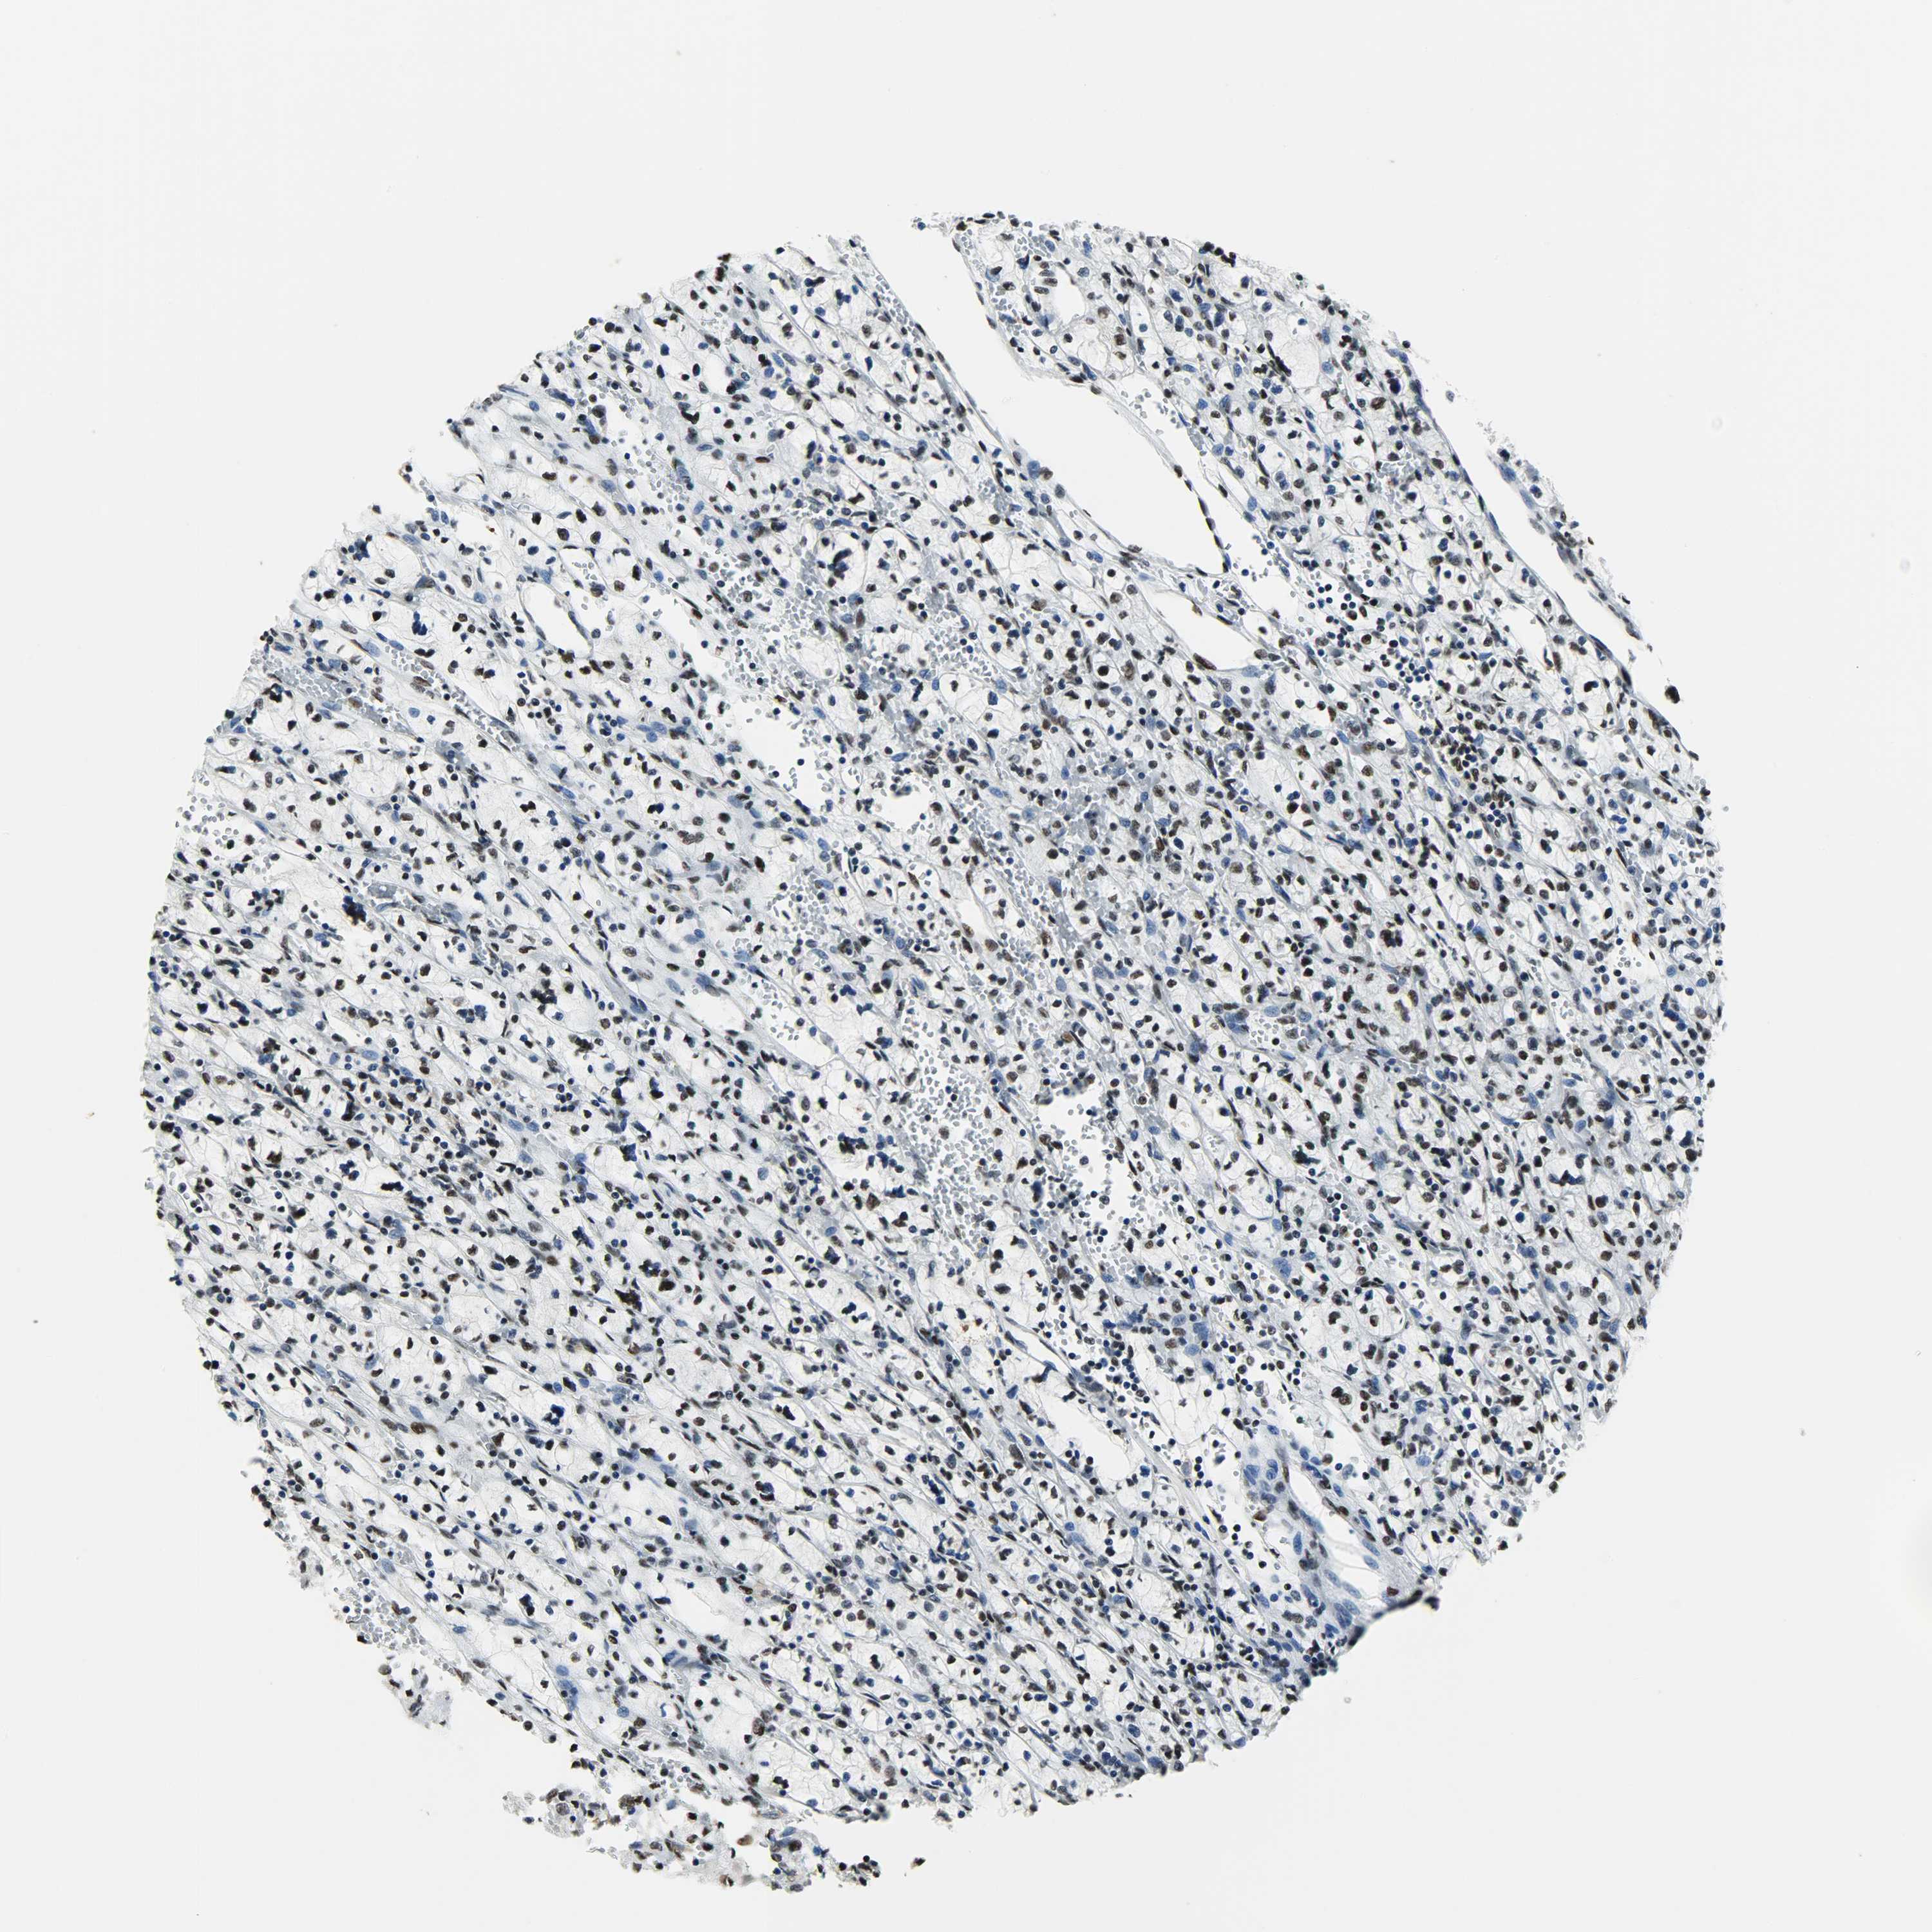

KIDNEY RENAL CLEAR CELL CARCINOMA (VALIDATION) - Interactive survival scatter ploti

The Survival Scatter plot shows the clinical status (i.e. dead or alive) for all individuals in the patient cohort, based on the same data that underlies the corresponding Kaplan-Meier plots. Patients that are alive at last time for follow-up are shown in blue and patients who have died during the study are shown in red.

The x-axis shows the expression levels (FPKM) of the investigated gene in the tumor tissue at the time of diagnosis. The y-axis shows the follow-up time after diagnosis (years). Both axes are complimented with kernel density curves demonstrating the data density over the axes. The top density plot shows the expression levels (FPKM) distribution among dead (red) and alive patients (blue). The right density plot shows the data density of the survived years of dead patients with high and low expression levels respectively, stratified using the cutoff indicated by the vertical dashed line through the Survival Scatter plot. This cutoff is automatically defined based on the FPKM cutoff that minimizes the p-score. The cutoff can be changed by dragging the vertical line or by entering a cutoff value in the square labeled "Current cut-off".

Under the Survival Scatter plot the p-score landscape (black curve; left axis) is shown together with dead median separation (red curve; right axis). Dead median separation is the difference in median mRNA expression between patients who have died with high and low expression, respectively. It is calculated as follows: median FPKM expression of dead patients with high expression - median FPKM expression of dead patients with low expression. This is intended to aid the user in visually exploring custom cutoffs and the associated p-scores and dead median separation.

Individual patient data is displayed and can be filtered by clicking on one or more of the category buttons on the top of the page. Categories describing expression level and patient information include: high, low, alive, dead, female, male and tumor stages. The scale of the x-axis can be toggled between linear and log-scale by clicking on the "x log" button. Mouse-over function shows TCGA ID, patient information and mRNA expression (FPKM) for each patient.

& Survival analysisi

Kaplan-Meier plots summarize results from analysis of correlation between mRNA expression level and patient survival. Patients were divided based on level of expression into one of the two groups "low" (under cut off) or "high" (over cut off). X-axis shows time for survival (years) and y-axis shows the probability of survival, where 1.0 corresponds to 100 percent.

SSB is not prognostic in Kidney Renal Clear Cell Carcinoma (validation)

Best expression cut offi

Based on the FPKM value of each gene, patients were classified into two groups and association between prognosis (survival) and gene expression (FPKM) was examined. The best expression cut-off refers the FPKM value that yields maximal difference with regard to survival between the two groups at the lowest log-rank P-value. Best expression cut-off was selected based on survival analysis .

When clicking on this number, the vertical dashed line indicating cut-off, the interactive survival plot, and the Kaplan-Meier curve will be adjusted to show results based on the best expression cut-off.

: 95.72

TCGA RNA samplesi

RNA-seq data is reported as average FPKM (number Fragments Per Kilobase of exon per Million reads), generated by the The Cancer Genome Atlas (TCGA) .

Normal distribution across the dataset is visualized with box plots, shown as median and 25th and 75th percentiles. Points are displayed as outliers if they are above or below 1.5 times the interquartile range. FPKM values of the individual samples are presented next to the box plot.

Average pTPM 97.3

Number of samples 100